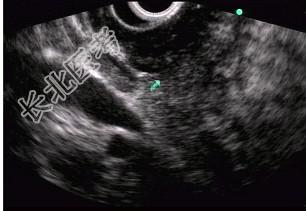

- 单项选择题男性,50岁, 上腹隐痛,食欲不振3个月。1个月来出现黄疸且进行性加深, 体重明显减轻,查体全身明显黄染, 肝未触及,深吸气时可触到肿大胆囊底部, 无触痛。化验血胆红素15mg/dl,尿检胆红素阳性图中胰腺病变可能的诊断是 ( )

E、胰腺癌